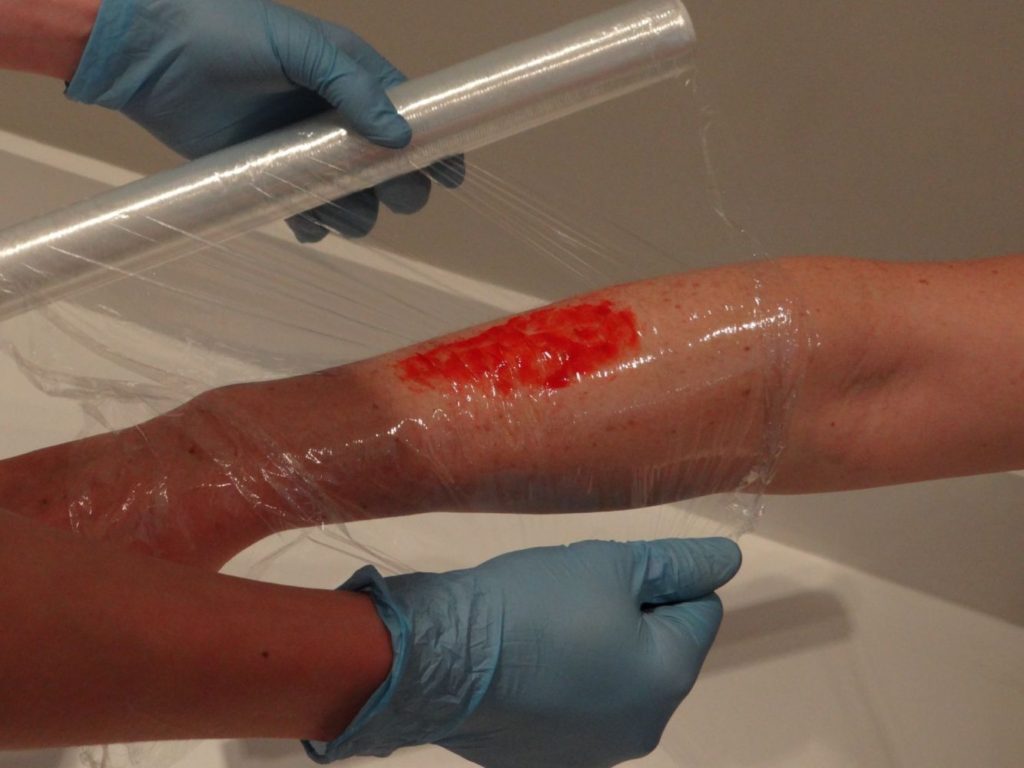

- Burns